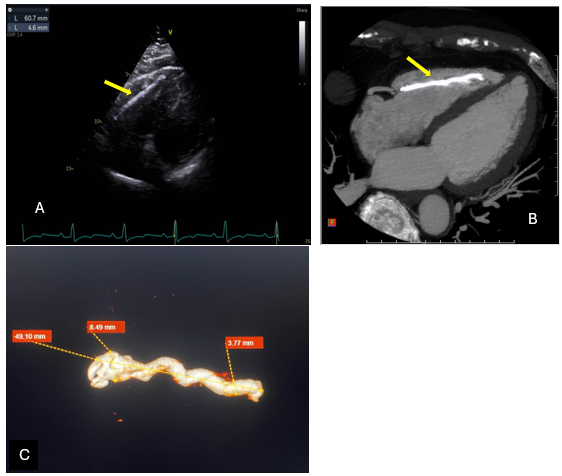

Khám lâm sàng ghi nhận bệnh nhân tỉnh, tiếp xúc tốt, tổng trạng tốt (BMI 25), sinh hiệu M: 68 lần/phút, HA: 150/90 mmHg, SpO₂ 98%. Ngoài khớp vai phải đau, các sinh hoạt thường ngày của bệnh nhân không gây đau ngực hay khó thở. Khám bệnh nhân niêm hồng, không phù, tim đều, rõ, không âm thổi, phổi không ran, thông khí đều hai bên, bụng mềm, gan không to, không điểm đau. Vai phải đau và hạn chế cử động. ECG ghi nhận nhịp xoang 65 lần/phút, sóng T âm từ V2 đến V5. MRI vai phải cho thấy rách gần toàn bộ gân cơ trên gai, viêm nhiều gân quanh khớp và thoái hóa khớp cùng – đòn. Siêu âm tim ghi nhận EF 46%, hình ảnh có cấu trúc dài tăng âm bất thường trong thất phải tương ứng với tổn thương trên CT, hở van 2 lá nhẹ, hở van 3 lá nhẹ, áp lực động mạch phổi bình thường (PAPs= 30 mmHg).

Hình 2: Hình ảnh dị vật tăng sáng dài nằm trong buồng thất phải, kích thước 55 x 3 mm, ít di động (mũi tên vàng). A: Hình siêu âm tim; B: Hình chụp cắt lớp vi tính tim; C: Hình ảnh dị vật xi măng xương sau khi xoá bỏ phần cơ tim trên phim MSCT.